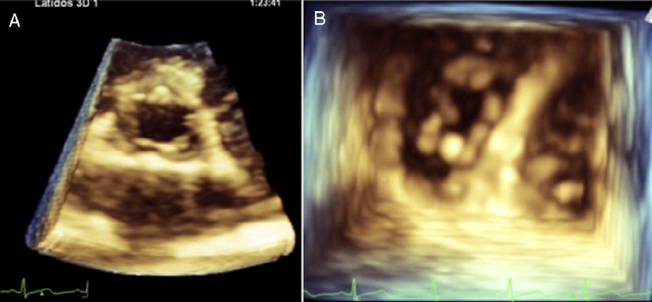

MLG is a female 58 years old with a history of rheumatoid arthritis diagnosed in December 2011 based on elevated rheumatoid factor, erythrocyte sedimentation rate and C-reactive protein, the presence of anticyclic citrullinated peptide antibody (anti-CCP), and bony erosions in the hands. She initially received treatment with immunosuppressors (methotrexate) and later with biological (abatacept) therapy with improvement and remission of the disease. She presented to the emergency room of our institution with a 3 weeks-history of a progressive dyspnea from great to moderate efforts, palpitations, fever (38.8 ◦C), malaise, dry cough and headache. On examination, she was tachycardic (HR: 101/min), with oxygen desaturation (P02 = 70%) and had bibasilar lung rales. The laboratory analysis showed leukocytosis (21.4 × 103/m3) and mild anemia (Hb – 12.7 g/dL and Htc – 40%). Blood cultures were negative. The chest computed tomography showed areas of bilateral alveolar occupation in relation to acute inflammatory process without pleural effusion. The transthoracic bidimensional (Fig. 1A–F) and three-dimensional echocardiogram revealed nodular thickening on the both mitral leaflets and in the subvalvular apparatus of the mitral valve without mitral regurgitation (Fig. 2A and B), small nodules in the aortic leaflets (Fig. 3A and prominent nodules on the tricuspid valve with mild tricuspid regurgitation (Fig. 3B), mild pulmonary hypertension, left ventricular diastolic dysfunction type I and normal left ventricular systolic function. The patient was treated with intravenous steroids and broad spectrum antibiotics with clinical improvement, but without changes in the valvular lesions. Actually she is in NYHA functional class I and the chest radiograph after the resolution of infectious process showed interstitial lung bilateral thickening and reticulonodular parahiliar and basal pattern, the left cardiac profile is abnormal and the aorta unrolled (Fig. 4).

Figure 3 Transthoracic three-dimensional echocardiogram of the aortic valve with small nodules in the edges (A). Transthoracic three-dimensional ventricular view of the tricuspid valve in diastole, showing prominent nodules in their cusps (B).

Among those extra-articular features of RA are cardiovascular diseases, including pericarditis, myocardial disease, coronary vasculitis, diastolic dysfunction, accelerated atherosclerotic disease and valvular lesions.7 In the literature the prevalence of RA valvular heart disease varies from 3% to 70%.8 Valvular lesions in RA result from non specific inflammatory process in the valvular base followed by fibrosis and, sometimes, calcification. Rheumatoid granulomata are more specific findings that can be found within cusps causing valvular insufficiency.8 In a study of 184 patients with RA, the valvular lesions were monovalvar and the aortic valve was the most affected.4 In comparison to this study, our case is very rare, because it had multivalvular cardiac nodules, small in aortic valve, of moderate size in mitral leaflets with involvement of mitral apparatus and more prominent in tricuspid valve.

Actually, three-dimensional echocardiography has been conceived as one of the most promising methods for the diagnosis and follow-up of valvular heart disease. In particular, for mitral valve diseases, this new approach has proven to be the most unique, powerful, and convincing method for understanding the complicated anatomy and dynamism of the mitral valve and also of the other cardiac valves.11 This technique should be performed in RA, because the resolution of the nodules is very clear as we observed in our patient. It has been shown that untreated systole in patients with RA is an important problem and joint efforts of rheumatologists and cardiologists may help to improve the cardiovascular morbidity and mortality in RA.5,8